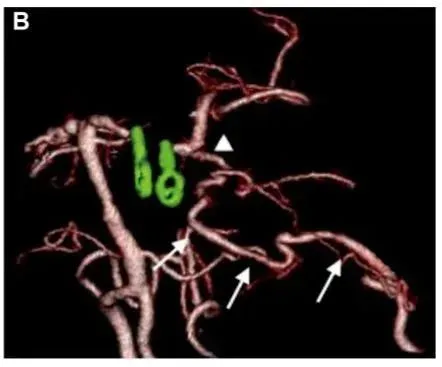

深处藏着“梭形炸弹”:左侧P1-P2交界处动脉瘤,大小10×12mm,形态不规则,术前3D-DSA图像清晰显示动脉瘤位于后循环关键区域(如图),一旦破裂,将危及生命。

术前3D-DSA显示位于左侧P1-P2交界处动脉瘤。

术后3D CTA显示左侧PCA区血管穿支(箭头)和重建的PTA血管(箭头)的血流通畅。